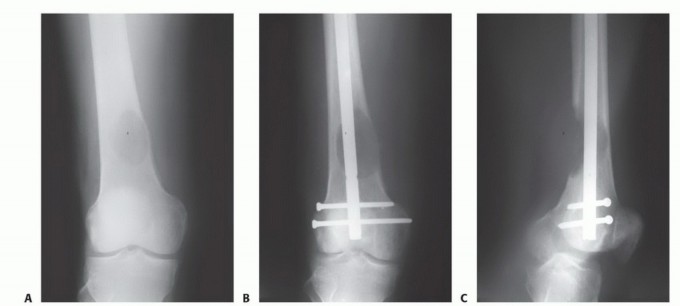

الأشعة السينية والتصوير المقطعي المحوسب CT

يجب إجراء صور الأشعة السينية العادية والتصوير المقطعي المحوسب (CT) للموقع المصاب، بالإضافة إلى صور الأشعة السينية العادية لأي موقع إضافي يبلغ فيه المريض عن ألم في المفصل أو العظم. ستحدد النتائج المجمعة لهذه الدراسات مدى تدمير العظام وامتداد الأنسجة الرخوة.

الشكل 1: أ. صورة أشعة سينية تظهر ورمًا نقيليًا في الحُق الأيمن لدى رجل يبلغ من العمر 72 عامًا ولديه تاريخ معروف بسرطان الغدة الدرقية. ب. يظهر التصوير المقطعي المحوسب (CT) تدميرًا واسعًا للعظام وامتدادًا للأنسجة الرخوة. محاولة الاستئصال بناءً على النتائج الشعاعية وحدها قد تؤدي إلى استئصال جزئي للآفة ونزيف محتمل بسبب الأوعية الدموية الكثيفة لهذا الورم. بالنظر إلى هذه النتائج الشعاعية، خضع هذا المريض لانسداد وعائي قبل الجراحة مما قلل من فقدان الدم أثناء الجراحة وسمح باستئصال ناجح.

إذا كانت النقيلة قيد الفحص تقع في عظم طويل، فيجب أيضًا إجراء صور أشعة سينية ذات جودة معقولة لكامل امتداد العظم لاستبعاد وجود نقائل إضافية؛ لأن هذه البيانات حاسمة للتخطيط الجراحي. قد تتسبب النقائل التي لم تُكتشف في كسور مرضية عند تحمل الوزن بعد الجراحة وتتطلب جراحة واسعة لإصلاحها.